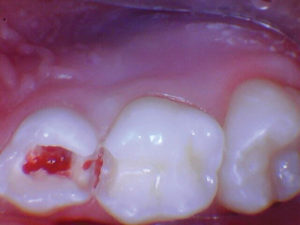

Caso 6

Una niña de 2 años presentó lesiones cariosas en todos sus molares primarios. Las opciones de tratamiento se discutieron con el cuidador principal del paciente, que incluyó: atención domiciliaria mejorada solamente, anestesia general para atención restaurativa o tratamiento con fluoruro de diamina de plata. El médico del paciente eligió el fluoruro de diamina de plata.

Figura 1. Presentación posterior a FDP de los molares primarios inferiores derechos que muestran lesiones detenidas.